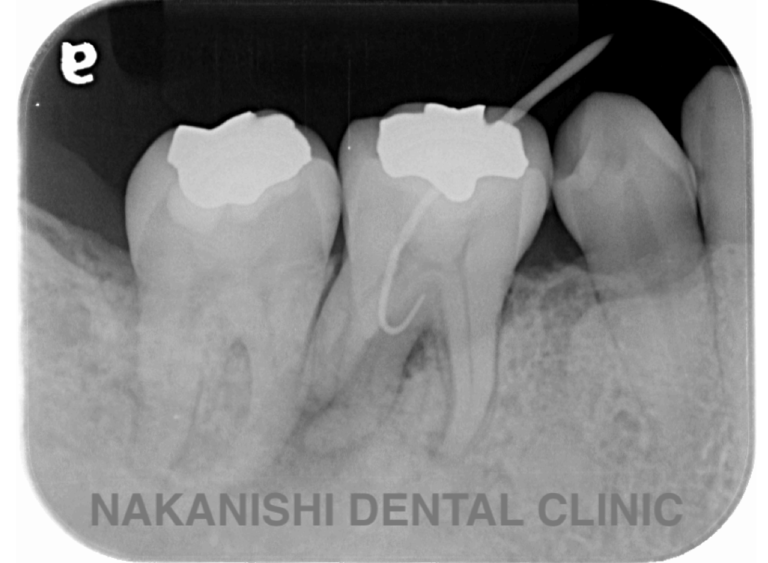

治療前

治療後

| 主訴 | 左下歯ぐきの腫れ。 |

|---|---|

| 治療期間 | 約2か月 |

| 治療費 | 約1万5千円 |

| 治療内容 | ラバーダム、マイクロスコープ下にて根管治療を施術。 歯ぐきの腫れ、痛みや違和感が消失したため根管充填、支台築造(土台の製作)を行った。治療後の写真は矯正治療を行うことになったため仮歯を装着した状態。 |

| 治療のリスク | マイクロスコープやCTを使用し、可能な限り精密な根管治療を行っていますが、歯根の形態や病変の大きさ、過去の治療履歴などにより、治癒が得られない場合があります。また、治療後に再感染や歯根破折が生じることもあり、その場合は再治療や抜歯が必要となることがあります。 治療結果には個人差があり、すべての症例で同様の経過を保証するものではありません。 |